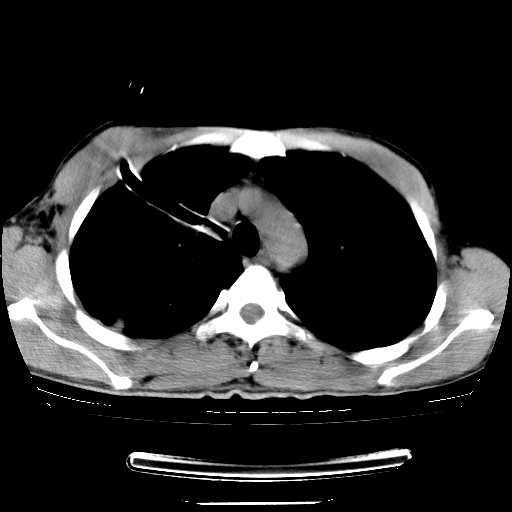

以下是引用dyqct在2008-4-29 8:43:00的发言:[br][br] 支持右侧胸腔包裹性积血。闭式引流管是不是插的太深了?

以下是引用zjzjr在2008-4-29 14:11:00的发言:[br]支持右侧胸腔包裹性积血。闭式引流管是不是插的太深了?胸腔引流,引流管快进入纵隔了.